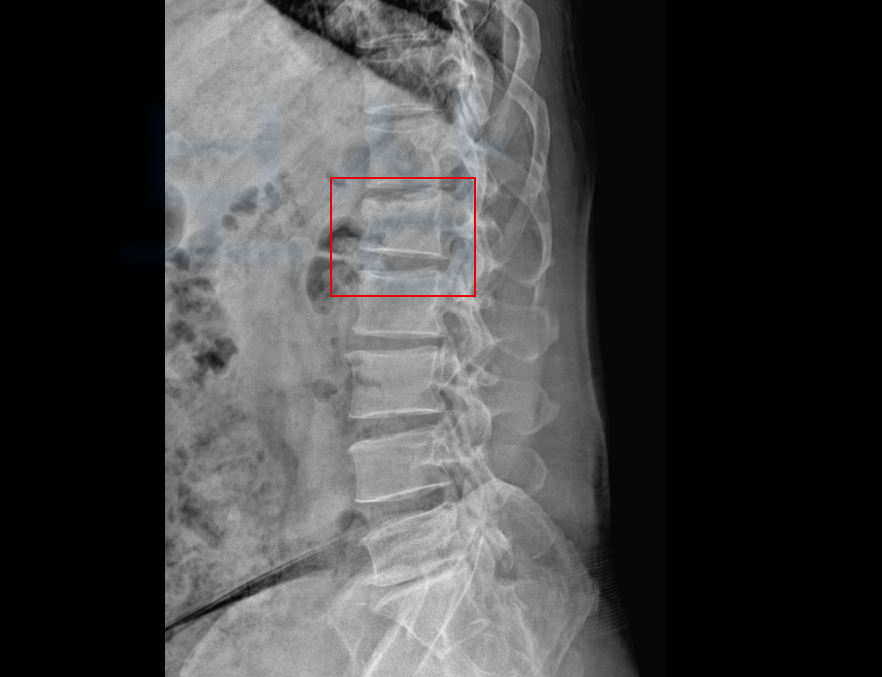

상기 의뢰인은 3M 높이에서 추락 사고 당하며 응급실 내원하게 되었습니다.

넘어진 이후 극심한 허리 통증에 정밀 검사를 시행한 결과

요추 1번 압박골절 s32090 진단받게 되었죠. 다행인지, 손@@님은 약 3개월간 TLSO 허리 보조기를 착용하며 보존치료를 진행하게 되었는데요, 하지만 3개월이 지났어도 여전히 허리는 욱신하고 통원치료를 계속 다니셔야 했습니다.